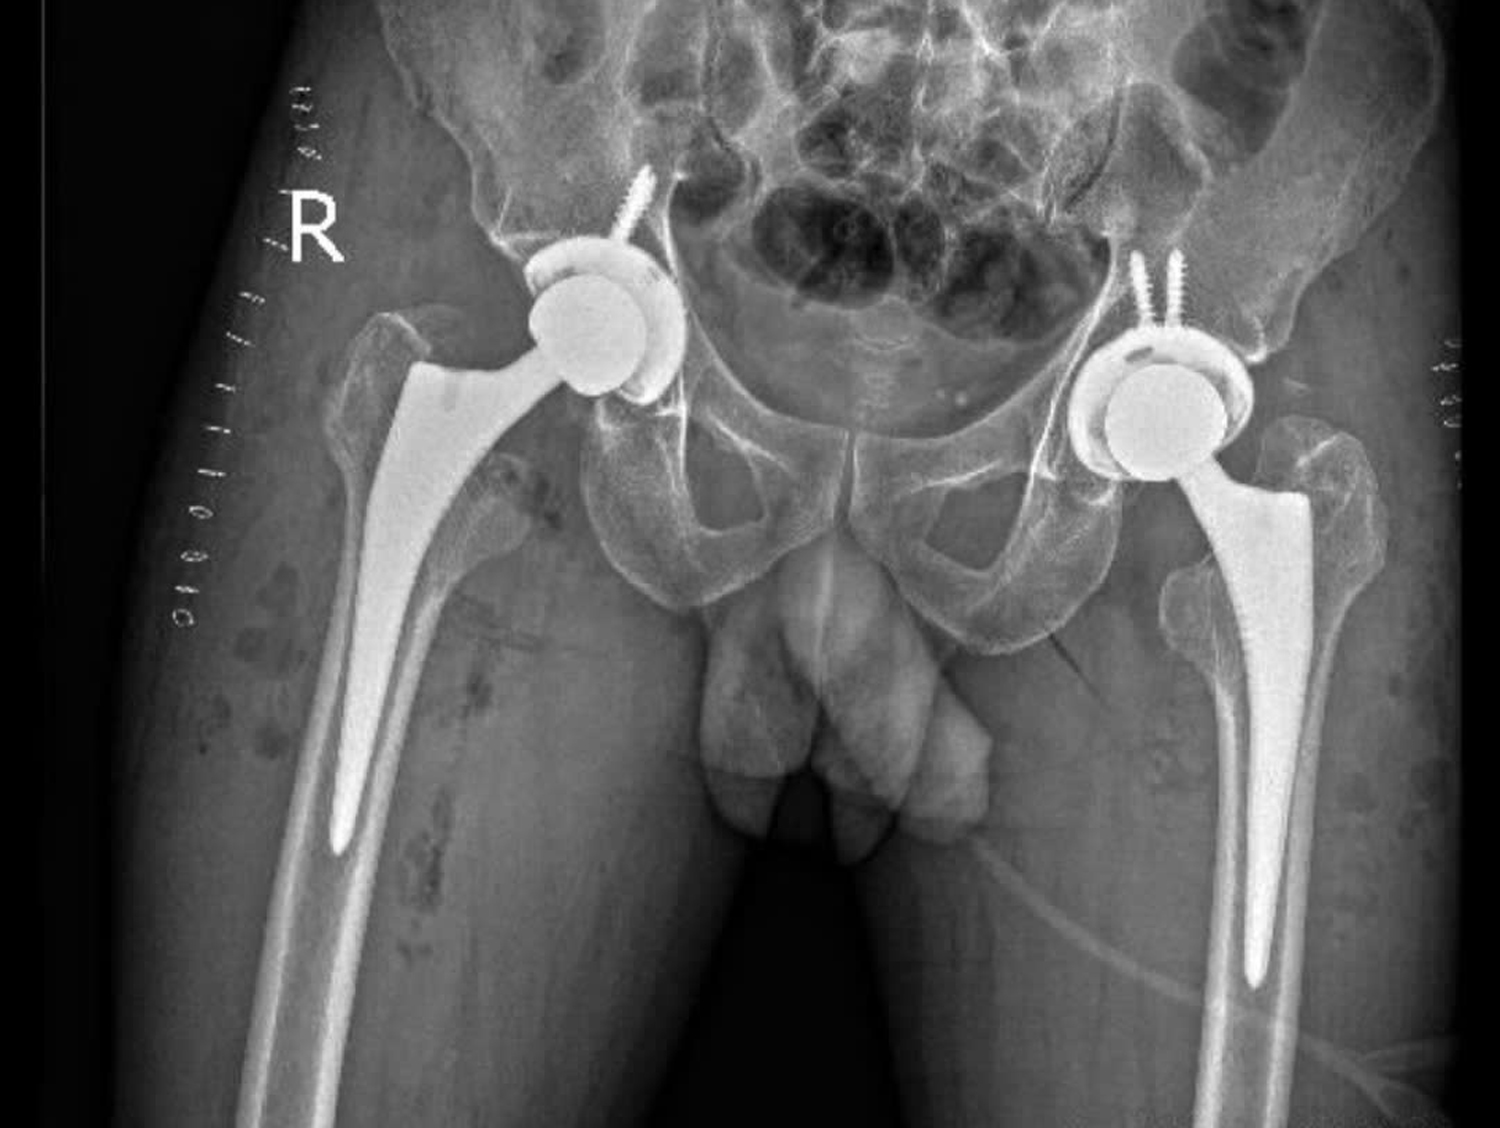

X-Quang khung chậu kiểm tra sau phẩu thuật.

Các bác sĩ đã lựa chọn đường mổ trực tiếp phía trước – phương pháp phẫu thuật ít xâm lấn trong thay khớp háng. Ca mổ kéo dài khoảng 4 giờ, tiến hành thay khớp háng hai bên trong cùng một lần phẫu thuật.

Sau phẫu thuật, bệnh nhân phục hồi thuận lợi và đến ngày thứ 2 đã có thể tập đi lại với khung hỗ trợ. Đến ngày thứ 5, ông P. tự đi, không cần dụng cụ hỗ trợ và dự kiến ra viện ngày 11/3.